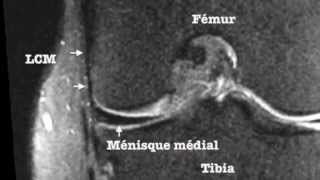

Le genou commenté : ménisques, ligaments croisés, ligaments latéraux, traumatologie des croisés

Anatomie 3D Lyon - 4 years ago